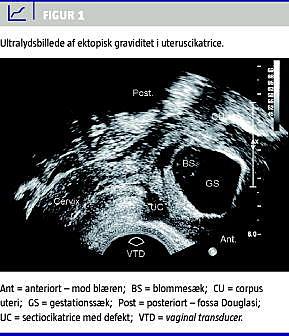

2. GS lokaliseret anteriort på niveau med synlig eller sandsynlig lokalisation for UC (Figur 1 )

Transvaginal 3D-UL kan ligeledes anvendes til at visualisere anatomiske detaljer, så som det veludviklede trofoblastiske væv og peritrofoblastisk flow omkring GS [23, 24]. Det tynde myometrium mellem blæren og graviditeten kan vurderes, og endelig kan man se, at GS ikke er sammenfalden eller uregelmæssig, hvilket ofte ses ved en igangværende abort [4]. Ved sidstnævnte vil man ved transvaginal UL og colour flow -Doppler finde en avaskulær GS i modsætning til den velvaskulariserede CSP. Lokalisationen af GS og eksponentielt fald i humant choriongonadotropin (hCG) kan anvendes til at differentiere mellem diagnoserne [4]. Differentialdiagnostisk vil en cervikal graviditet ved transabdominal UL (fyldt blære) præsentere sig med GS placeret i cervix og et tyndt endometrie i den tomme timeglasformede uterus [25].